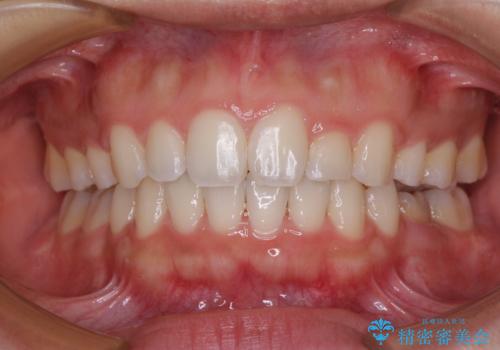

【モニター】捻れた前歯をスッキリと インビザライン矯正治療

担当医 藤巻太一朗